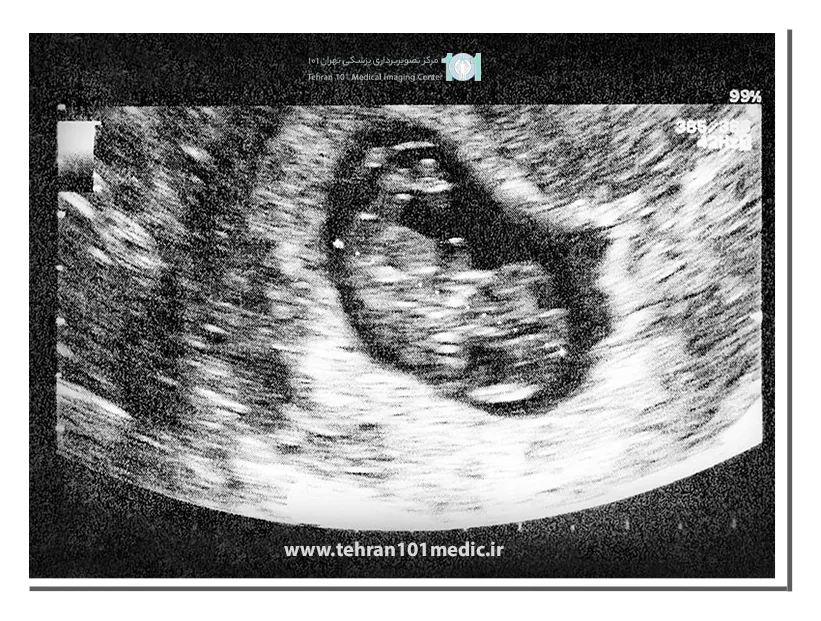

ضربان قلب جنین از هفته پنجم یا ششم بارداری شروع به زدن کرده که ممکن است از طریق سونوگرافی تشخیص داده شود که معمولا از سونوگرافی ترانس واژینال برای تشخیص آن استفاده میشود. بهترین زمان سونوگرافی برای ضربان قلب جنین از هفته دهم بارداری است که مادر در ماه سوم به سر میبرد.

به طور کلی در سونوگرافی شکمی از ۷ هفتگی و در سونوگرافی واژینال از ۶ هفتگی صدای ضربان قلب جنین قابل شنیدن است. در هفته دهم به بعد قلب جنین به طور کامل شکل گرفته است. اینکه دقیقا از چه زمانی بتوان ضربان قلب جنین را شنید به وضعیت جنین در رحم، وزن مادر و دقیق بودن موعد زایمان دارد.